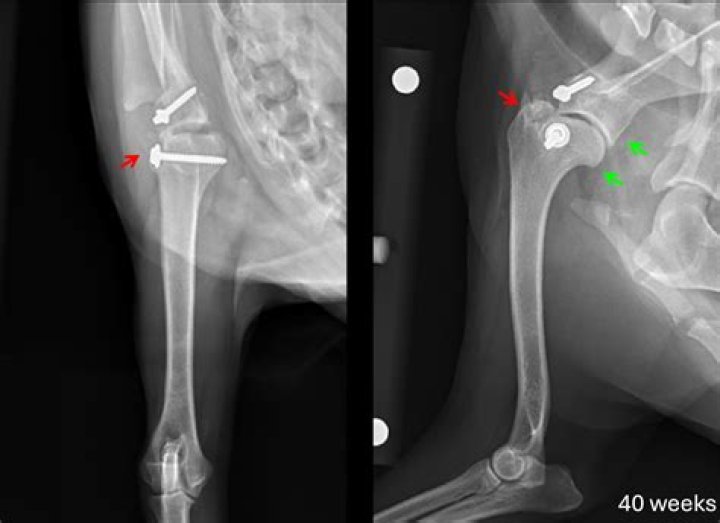

Cost of Arthroscopic Surgery in Dogs The cost of arthroscopic surgery can range from $1,500 to $4,000. The need for specialized equipment generally results in a higher cost. A surgeon who has received extra training for performing these types of surgeries is also necessary.